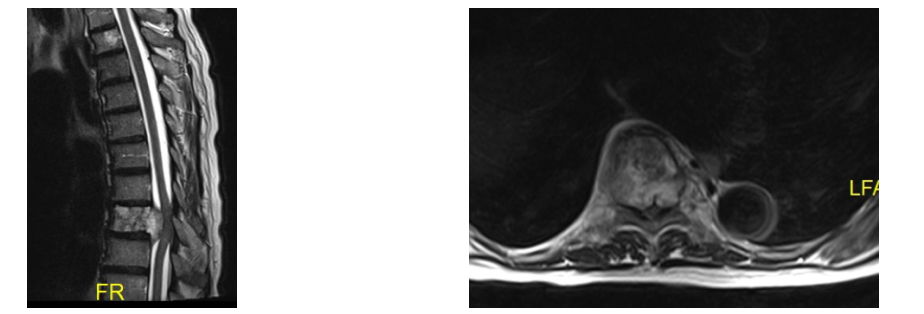

Spondylitis/Spondylodiszitis

Eine bakterielle Knochenentzündung der Wirbelsäule (Spondylitis) mit Übergreifen auf die Bandscheibe (Spondylodiszitis) kann unterschiedliche Entstehungsursachen haben. Bei der häufigeren Form der endogen verursachten Knocheneiterung kommt es zu einer Streuung von Bakterien über die Blutbahn mit Absiedlung in den Wirbelkörper. Entsteht eine Knocheneiterung nach Operation oder Infiltration im Bereich der Wirbelsäule, so spricht man von einer exogen verursachten Entzündung.